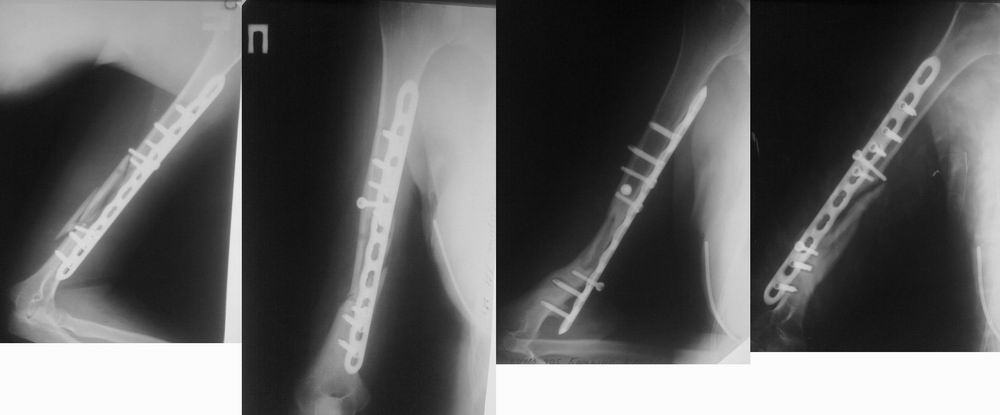

Исходный снимок

Снимки в динамике